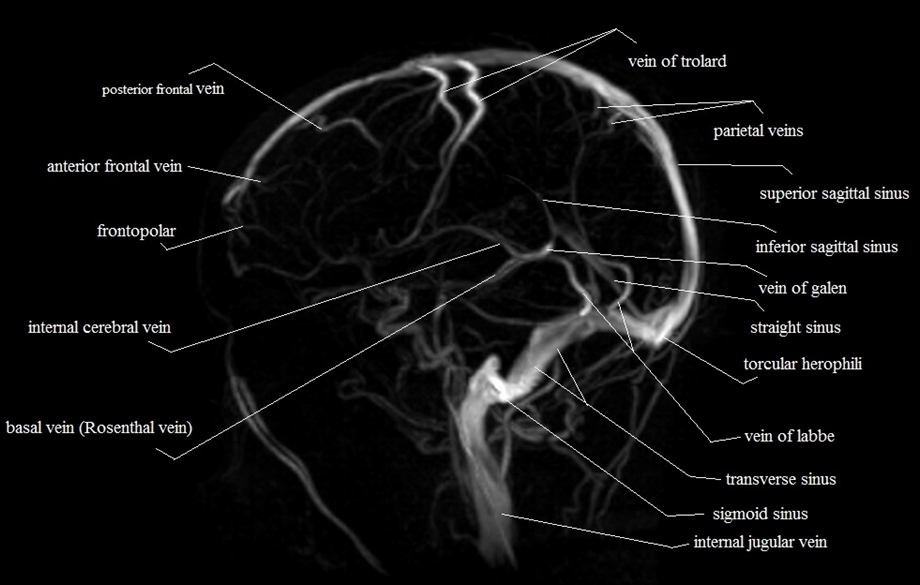

MR Venography

Investigation of choice in suspected Cerebral Venous sinus

thrombosis. Can show obstructed sinus and thrombosis within and absence

of flow